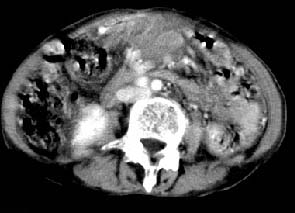

肝胃之间、肝十二指肠韧带,胰头后、腹主a周围,融合而成团块状影,包绕血管[腹腔干、肠系膜上动脉,腹主动脉],胰腺前移后缘分界欠清,与肝胃分界清,肿块未见明显强化,肝右叶后段小囊肿。

主动脉-胰腺间隙可见巨大分叶状软组织肿块影,包绕腹主动脉、腹腔干及其分支、腔静脉等大血管,增强呈无明显强化,临近脏器明显受压移位,增强示有分界。肝右叶可见局限性低密影,边缘清楚。

考虑腹膜后淋巴瘤。

影象表现:平扫,首先可见胃壁明显增厚,内外边缘清晰,外缘光滑,内边缘不归整,同时胃腔明显缩小。

再看从肠系膜根部到胰腺后主动脉及上腔静脉周围可见相连的较大的软组织肿块影,形态不规则,呈明显

的大小不等的分叶状,其中密度较均匀但其中可见条状低密度区,肿块边缘比较清晰周围的小肠受压移位

明显且堆积。

增强所见,腹腔动脉,肠系膜上动静脉被肿块包绕,结合平扫的条状低密度区恰好位于血管周围,较大的

肿块强化不明显(遗憾的是没有标上ct值)但胃壁强化的十分明显。

影象诊断:考虑淋巴瘤待除外胃癌腹膜后淋巴结转移

讨论:首先看肠系膜和腹膜后的肿块我认为是多发融合的肿大的淋巴结。理由1大小不等的分叶,分布比较

自由。2其中的包绕的血管和周围少量的脂肪即所说的。

同时胃的影象表现和临床的不典型表现,所以我认为淋巴瘤,临床表现不支持胃癌